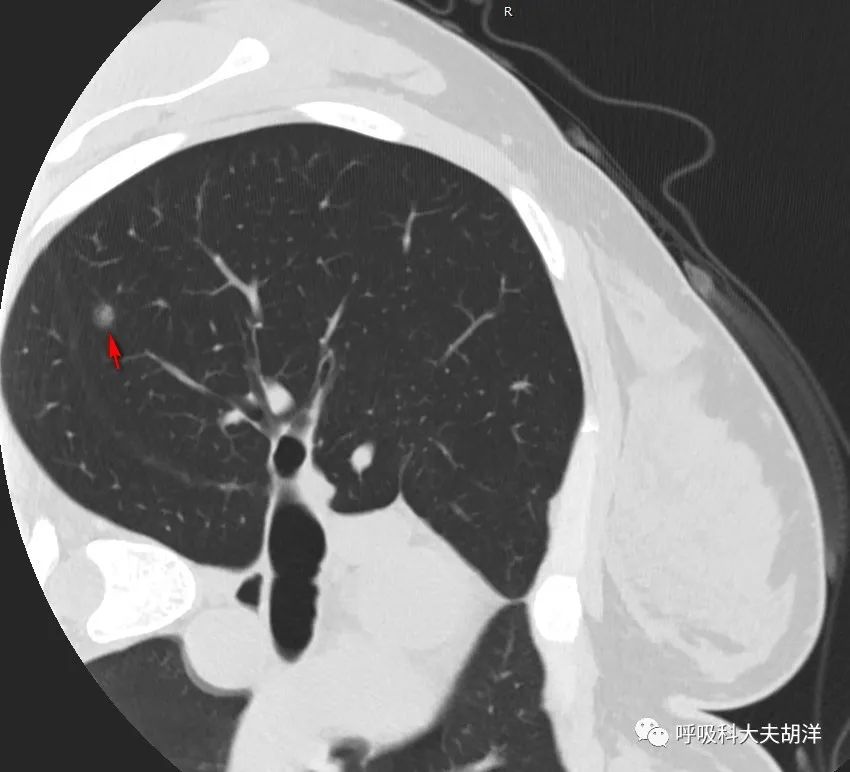

但这个结节偏恶性的特征还不止于此,上图结节的左面有一条线,这个是斜裂,斜裂是胸膜的一种延续,这个胸膜在靠近结节的部分微微向结节隆起,似乎有牵拉,这一层面看不明显,下图就比较明显了,箭头所指的部位是结节底部牵拉胸膜的征象,这是结节恶性特征的另外一个征象。

向下滑动查看上面三张图片则非常直观的看到结节牵拉斜裂的表现,结节靠近斜裂的地方像是被斜裂吸引,斜裂靠近结节的地方像是被结节吸引,整体上就像快要落山的太阳,太阳和水里的太阳的倒影几乎快连成一片,这是比较典型的胸膜牵拉。

如果想看结节和血管之间的关系,下面这几张图更加明显一点,下面前两张红箭头指的是结节,周围枝枝叉叉的都是血管,有些血管和结节长到了一起,尤其是最后一张图,另一个红箭头指着的血管长进了血管,这是结节代谢高,需要更多血液供应的表现,也是恶性肿瘤的一个表现。